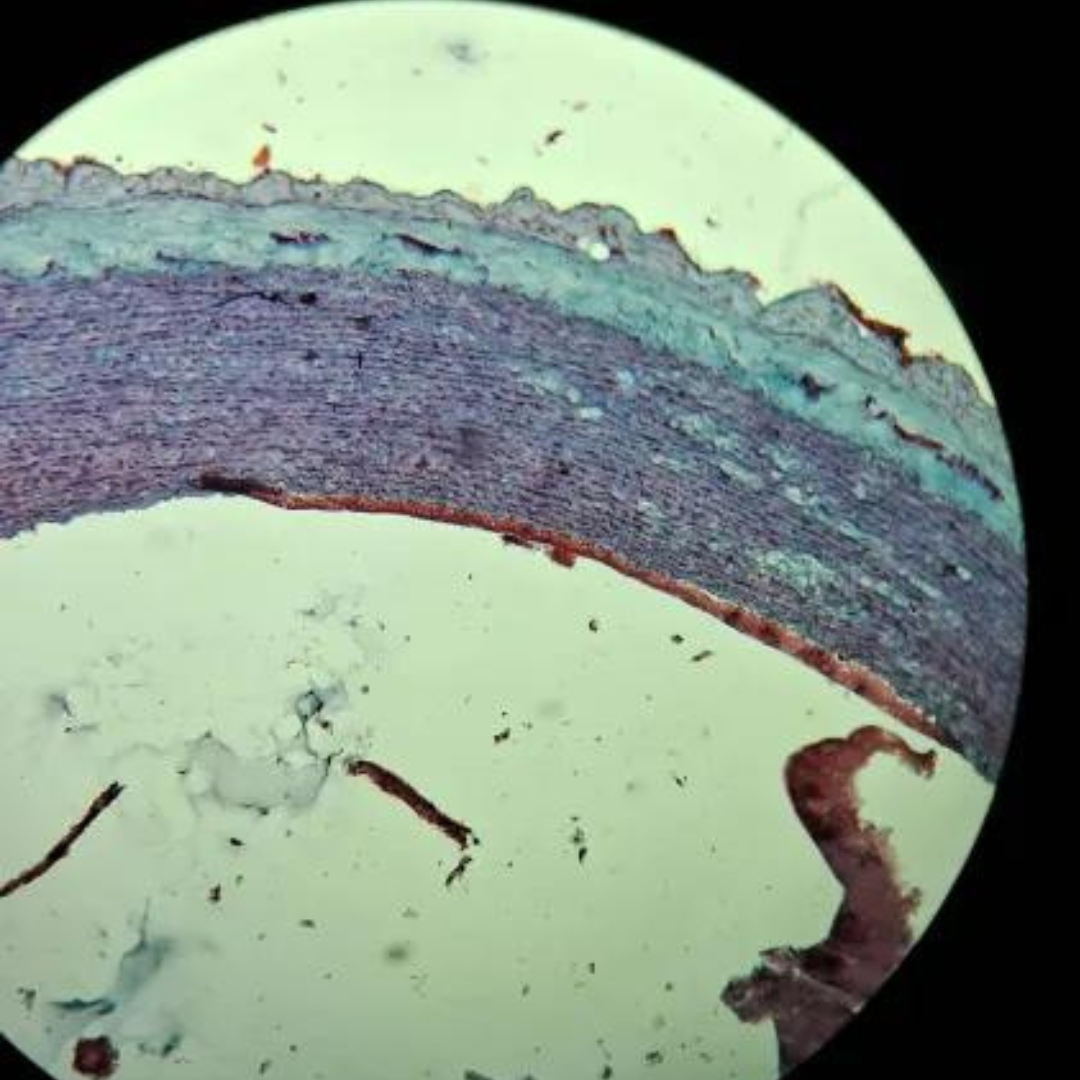

Elastic Arteries (Aorta)

Elastic Arteries (Aorta)

Elastic Arteries (Aorta)